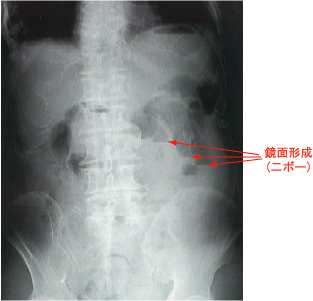

<腹部単純X線写真>

立位検査では鏡面像(二ボー,niveau)が見られます。

(98回医師国家試験C1)